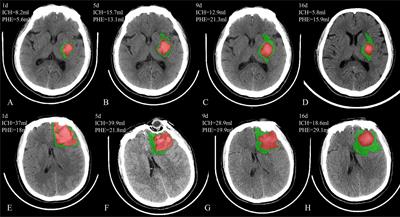

The association between blood pressure variability and perihematomal edema after spontaneous intracerebral hemorrhage